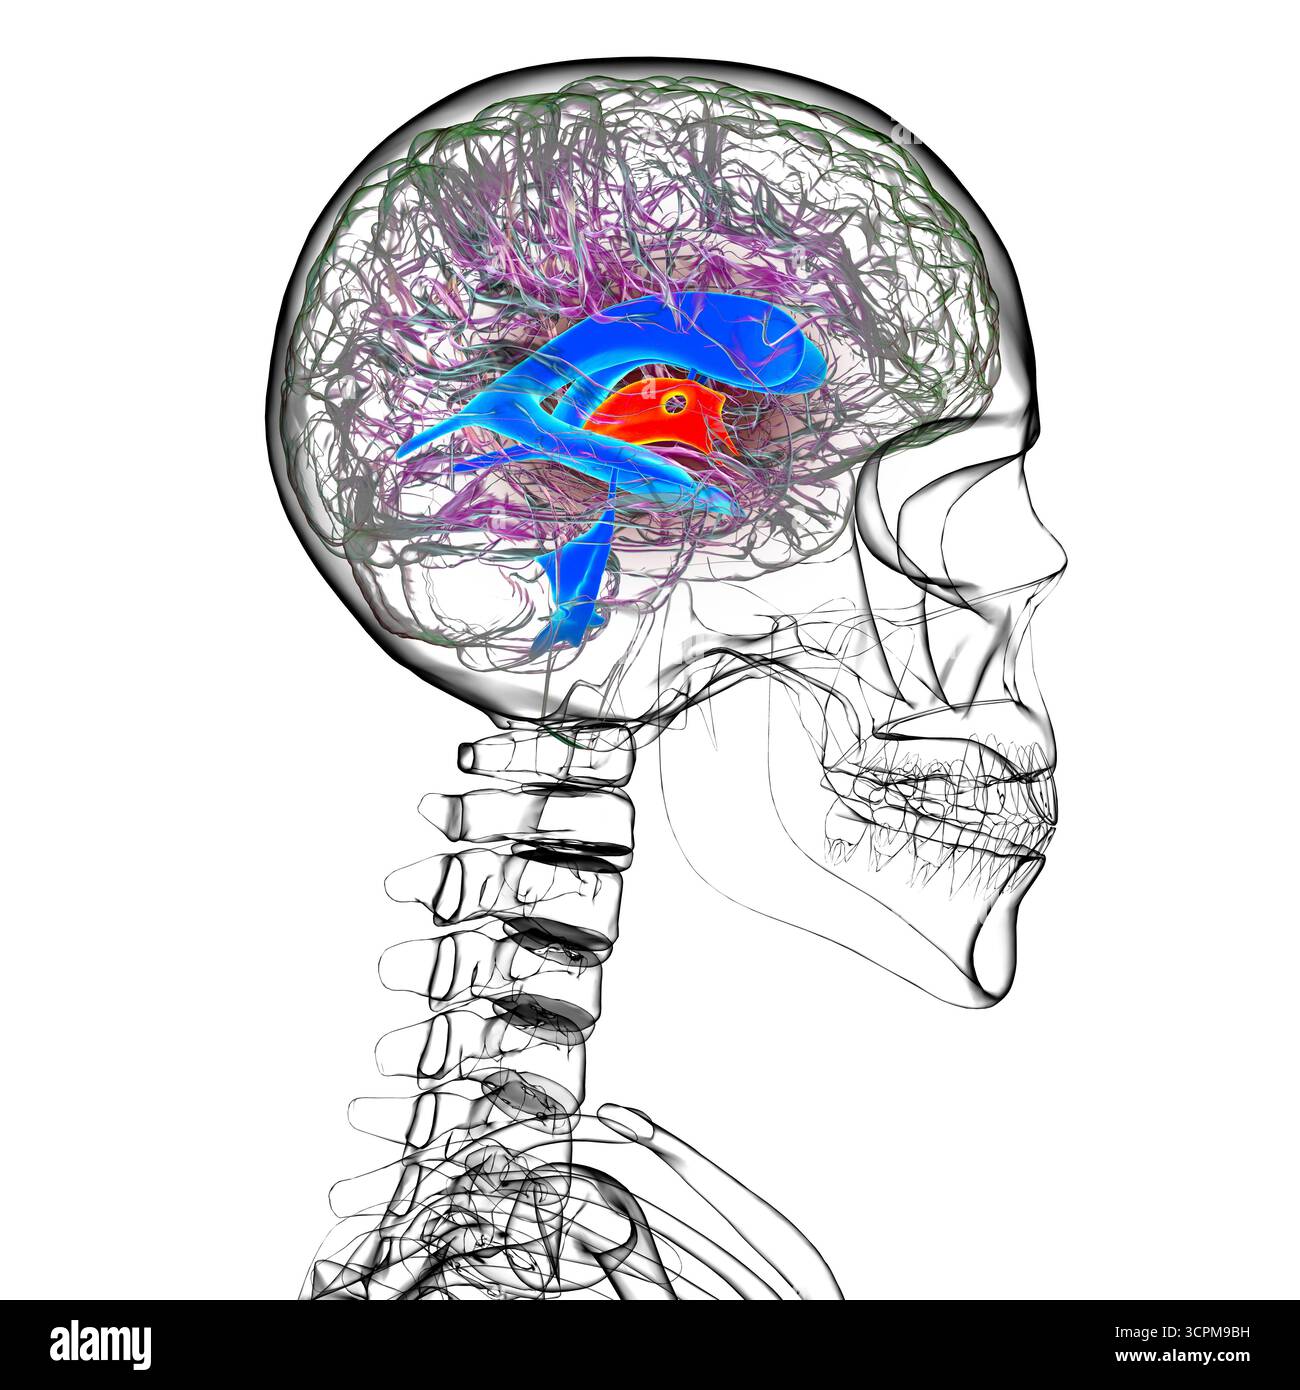

RF3CPM9C1–Illustration des dritten Hirnventrikels, einer lebenswichtigen Komponente des Hirnventrikulärsystems.

RF3CPM9BH–Illustration des dritten Hirnventrikels, einer lebenswichtigen Komponente des Hirnventrikulärsystems.

RF3CPM9BE–Illustration des dritten Hirnventrikels, einer lebenswichtigen Komponente des Hirnventrikulärsystems.

RF3CPM9BX–Illustration des dritten Hirnventrikels, einer lebenswichtigen Komponente des Hirnventrikulärsystems.